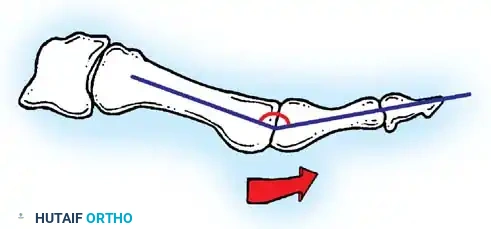

Hallux valgus (lateral deviation of the great toe) is not a single disorder, as the name implies, but a complex deformity of the fi rst ray that frequently is accompanied by deformity and symptoms in the lesser toes (Fig. 78-1). Often the angle between the fi rst and second metatarsals is more than the 8 to 9 degrees usually considered to be the upper limits of normal. The valgus angle of the fi rst metatarsophalangeal joint also is more than the 15 to 20 degrees considered to be the upper limits of normal (Fig. 78-2). If the valgus angle of the fi rst metatarsophalangeal joint exceeds 30 to 35 degrees, pronation of the great toe usually results. With this abnormal rotation, the abductor hallucis, which is normally plantar to the fl exion-extension axis of the fi rst metatarsophalangeal joint, moves further plantarward (Fig. 78-3). In this case, the only restraining medial structure is the medial capsular ligament with its capsulosesamoid portion (inserting into the base of the proximal phalanx) (Fig. 78-4) and capsulophalangeal portion (inserting into the plantar plate). The adductor hallucis, which is unopposed by the abductor hallucis, pulls the great toe further into valgus, stretching the medial capsular ligament (particularly the capsulosesamoid), attenuating this structure, and allowing the metatarsal head to drift medially from the sesamoids. In addition, the fl exor hallucis brevis, fl exor hallucis longus, adductor hallucis, and extensor hallucis longus increase the valgus moment at the metatarsophalangeal joint, further deforming the fi rst ray. The deep transverse intermetatarsal ligament runs between the plantar plates at the metatarsophalangeal joints and does not insert into bone on the adjacent sides of the metatarsal heads. Finally, the sesamoid ridge on the plantar surface of the fi rst metatarsal head (the crista) fl attens because of pressure (abutment) from the tibial sesamoid (Fig. 78-5). With this restraint lost, the fi bular sesamoid displaces partially or completely into the fi rst intermetatarsal space (see Fig. 78-2). In this situation, the patient is bearing less weight on the fi rst ray and more on the lesser metatarsal heads, increasing the likelihood of transfer metatarsalgia, callosities, and stress fracture of a lesser metatarsal.

Two other anatomical variants involving the articular surface of the fi rst metatarsophalangeal joint can lead to hallux valgus. In the fi rst variant, the articular surface of the metatarsal head is offset, resembling a scoop of ice cream sitting at an angle on a cone (Fig. 78-6). This has been described as the distal metatarsal articular angle (see Fig. 78-8). In the second, the articular angle of the base of the proximal phalanx in relation to its longitudinal axis is offset. This has been described as the phalangeal articular angle. Although the normal range of these angles is generally considered to be 7 to 10 degrees for the phalangeal articular angle and 10 to 15 degrees for the distal metatarsal articular angle, exact measurements are diffi cult to reproduce because of the variability of radiographic and measurement techniques. Increasing evidence indicates, however, that the failure to correct these two deformities, especially the distal metatarsal articular angle, can cause unsatisfactory results after surgery in some patients. Forceful straightening of the hallux should be avoided if it sacrifi ces tarsalgia. The entire forefoot must be evaluated for these multiple components of hallux valgus before surgical planning is complete and recommendations can be made to the patient. The controversy continues over which deformity is the essential lesion in hallux valgus: metatarsus primus varus or lateral deviation of the great toe. Each is incriminated as the cause of the other. The strongest data probably support lateral deviation of the great toe as the primary deformity in most patients, followed by medial angulation of the fi rst metatarsal, but metatarsus primus varus may be the principal cause in adolescents. Further controversy surrounds the role of footwear as the prime offender in the development of hallux valgus. Most orthopaedic surgeons have seen unilateral hallux valgus when both feet are clinically and radiographically the same structurally except that one foot has a bunion deformity and the other foot is normal. Evidence supports that hallux valgus may be familial, especially when it occurs in adolescents. Although no study of shod and unshod societies has implicated inappropriate footwear as the sole cause of hallux valgus, after genetic factors, binding, unphysiologically designed footwear probably is the major cause in modern societies. Hypermobility of the fi rst ray also has been suggested as a causative factor in the development of hallux valgus and fi rst metatarsal varus, but this is controversial. Coughlin and Shurnas, Myerson and Badekas, King and Toolan, and Faber et al. offer excellent discussions of this problematic area. Finally, certain anatomical and structural abnormalities almost certainly play a causative role in hallux valgus. Pronated fl atfeet, abnormal insertion of the posterior tibial tendon, increased obliquity of the fi rst metatarsomedialcuneiform joint, an abnormally long fi rst ray, incongruous articular surfaces of the fi rst metatarsophalangeal joint, and excessive valgus tilt of the articular surface of the fi rst metatarsal head and proximal phalangeal articular surface may contribute singly or in combination to the deformity and infl uence the recommended treatment. Hypertrophy of the medial eminence has been described as a component of hallux valgus deformity since the earliest reports; however, more recent investigations, including those of Thordarson and Krewer, have found that bony proliferation is not a component of the pathoanatomy of hallux valgus and that the prominence of the medial eminence results from the combination of metatarsus primus varus and medial deviation that uncovers the articular surface. Thordarson and Krewer compared radiographs of 50 feet in patients who had surgery for hallux valgus deformity with radiographs of 50 feet from a control group without hallux valgus deformity and found little difference in the average width of the medial eminence (4.4 mm and 4.1 mm). With more than 130 operations recommended for the treatment of hallux valgus, it is practical to describe only

Inadequate vascularity or sensibility should be investigated thoroughly before bunion surgery is considered. In addition, the position of the articular surface of the metatarsal head in relation to the longitudinal axis of the fi rst metatarsal should be determined (Fig. 78-8). Standard preoperative radiographs should include standing dorsoplantar and lateral views, a nonstanding lateral oblique view, and axial sesamoid views (Fig. 78-9). The hallux valgus angle and the fi rst-second intermetatarsal angle should fi rst be drawn on the standing dorsoplantar view by bisecting the shafts of the bones (Fig. 78-10), with an awareness of the normal ranges. These angles are most frequently cited as guidelines for treatment decisions, but Donnelly et al. reported that interobserver measurements of the hallux valgus angle varied by approximately 6 degrees and of the intermetatarsal angle by 4 degrees. They cautioned that potential errors in measurement should be considered when these parameters are used to make treatment decisions. The hallux valgus interphalangeus angle and any evidence of degenerative arthritic changes at the fi rst metatarsophalangeal or metatarsocuneiform joints should be documented. Oddities may be present and, if overlooked, may compromise a technically well-done procedure. Mann emphasized that the presence of an os inter-

Fig. 78-8 A, Determination of position of articular surface of metatarsal head in relation to longitudinal axis of fi rst metatarsal. B, Measurement of distal metatarsal articular angle at time of surgery. Markings are at medial and lateral margins of articular surface of fi rst metatarsal head and longitudinal axis of fi rst metatarsal shaft. metatarseum between the bases of the fi rst and second metatarsals might preclude the effectiveness of a soft-tissue procedure alone to provide suffi cient correction of the increased intermetatarsal angle. Likewise, accessory sesamoids and prominent ungual tuberosities at the interphalangeal joint contribute to a painful callus at the tibial side of this joint. An os tibialis externum frequently is associated with excessive hallux valgus interphalangeus. Varus of the fi rst metatarsal might be a signifi cant part of the overall deformity of the foot even with an intermetatarsal angle of less than 10 degrees. Metatarsus varus with a relatively small hallux valgus angle (15 to 20 degrees) may produce signifi cant deformity even though the angles are not excessive. The usefulness of computer-assisted compared with manual measurement of the intermetatarsal angle, hallux valgus angle, and distal metatarsal articular angle is still uncertain. Both methods have closer interobserver and intraobserver correlation in measurement of the intermetatarsal angle and hallux valgus angle than in measurement of the distal metatarsal articular angle. The reliability of either method has such a wide range (5 degrees), however, that measurements of these angles, although useful as a guide, do not provide a completely reliable indication of the magnitude of deformity. Condon et al. suggested that the reliability of the intermetatarsal angle can be improved by careful technique and by making the measurements at least twice and averaging them. Schneider et al. reported two methods of determining angular measurements based on distinctly different reference points: (1) a longitudinal axis of the fi rst metatarsal using middiaphyseal reference points, and (2) a center-head technique using a center head (center of the articular surface) and center base